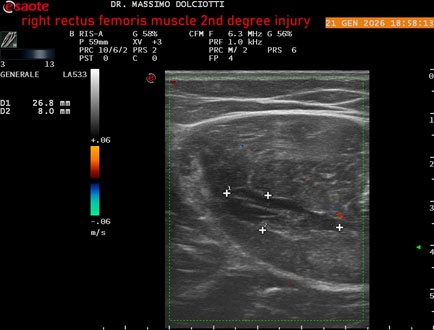

Data inserimento: 23/01/2026

Ecografia del: 21/01/2025

Strumento: Esaote MyLab Eight

Sonda: Lineare Multifrequenza 3-13 MHz

Età Paziente: M 23 anni

Motivazione dell'esame: dolore al terzo prossimale della coscia destra da tre giornii.

Commento all'esame: le immagini ed il video documentano, al terzo prossimale del muscolo retto femorale destro, area disomogenea, ipoecogena, delle dimensioni di 35 mm per uno spessore di 18 mm, misura ottenuta per asse corto o trasversale, e di 71 mm x 20 mm, misura ottenuta per asse lungo o longitudinale, da ricondurre a lesione muscolare di 2° grado con modica raccolta sieroematica intramuscolare.

Conclusioni: lesione di 2° grado del muscolo retto femorale destro (2nd degree injury of the right rectus femoris muscle).